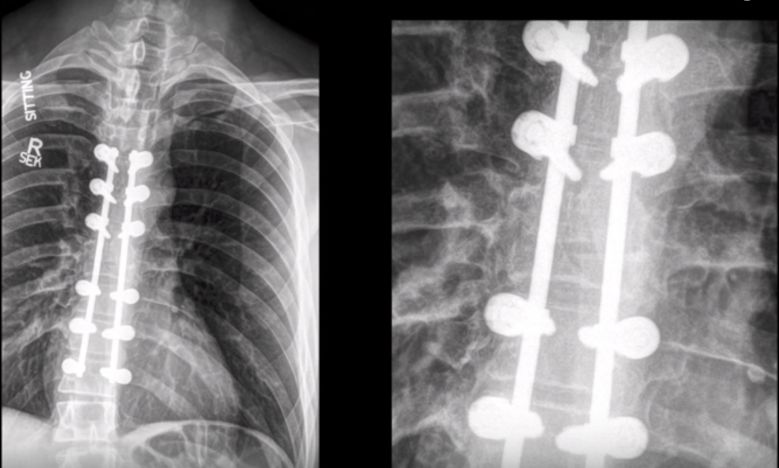

Jered Chinnock脊柱受伤术后X光(来源:304.cam永利集团梅奥诊所)

2013年2月的一次意外事故让Jered Chinnock下半身完全瘫痪,他失去了曾经理所应当的站立和行走能力。在那次意外中,他驾驶着雪地摩托发生了撞击事故,被甩下来之后又遭受了紧随其后的雪地摩托的二次伤害,这造成他多根肋骨断裂、脊柱骨折。他被迅速送往医院急诊,虽然进行了手术,但是却无法改变脊髓受损的状况,他瘫痪了。“我觉得我下半辈子都离不开轮椅了,”Jered Chinnock说,“我一直都希望能够重新走路,如果是你因为意外再也无法站起来了,你一定也希望能够再次行走。”